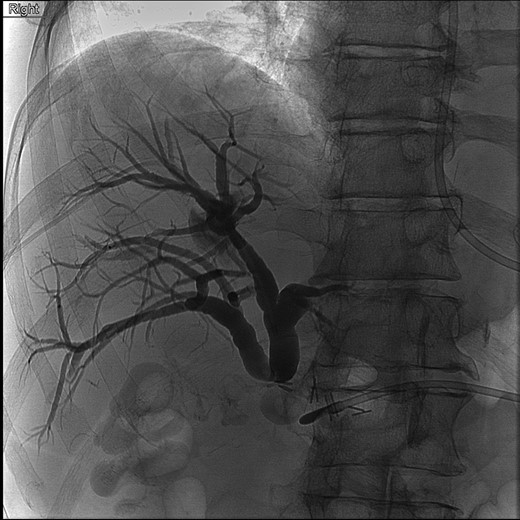

The patient was placed on broad spectrum antibiotics and treated for atrial fibrillation with rapid ventricular response. Laboratory workup revealed a bilirubin level of 17 mg/dl, as well as profound protein–calorie malnutrition with an albumin of 1.9 gm/dl. A percutaneous cholangiogram was performed confirming a hilar ligation of his hepatic duct with inability to pass a wire or catheter distally. A right posterior and right anterior percutaneous cholangiogram catheter was placed for definitive biliary diversion (Fig. 2). The patient was then managed with high calorie, high protein enteral nutrition through a nasogastric Dobhoff tube for approximately 7 days until able to tolerate appropriate oral intake for discharge. He was scheduled for follow-up in 2 weeks.

Cholangiogram of right intrahepatic ducts with abrupt cutoff at surgical clips.